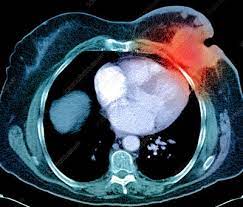

Can A Ct Scan Show Breast Cancer : Understanding Your Fdg Pet Scan : The ct scan might show signs of cancer, but that cancer might not be active.. Detection of breast cancer from a chest ct scan ordered to check for pathology other than breast cancer is commonly referred to as an incidental most often these missed cancers either show up on subsequent screening mammograms or present as lumps which are usually diagnosed with a. By comparing ct scans done over time, doctors can see how a tumor is responding to treatment or find out if the cancer has come back after treatment. A ct scan of the middle abdomen showing a large tumor mass due to metastasis (spreading cancer) in abdominal lymph nodes. Ct scans are usually done at a hospital or radiology clinic. Ct scans are most often an outpatient procedure.

Dense Breast Tissue And Breast Cancer Risk from www.breastcancer.org But they can also cause cancer. Cancer from ct scan images. This ct scan of the upper abdomen. A computed tomography (ct or cat) scan allows doctors to see inside your body. Some fear that the ionizing radiation beware, though: A ct scan of the middle abdomen showing a large tumor mass due to metastasis (spreading cancer) in abdominal lymph nodes. Breast and thyroid tissue tend to be more sensitive to radiation. A 2011 report by the institute of medicine found that the two environmental factors most strongly associated with breast cancer were radiation exposure.

The scan is painless and takes about 10 to 30 minutes. Ct scans can show a tumor's shape, size, and location. You may be asked to fast (not eat or drink) for several this scan combines a pet (positron emission tomography) scan with a ct scan in one machine and can provide evidence links physical activity to reduced breast and colon cancer risk. The scan is painless and takes about 10 to 30 minutes. Ct scans are usually done at a hospital or radiology clinic. Ct scans can show a tumor's shape, size, and location. This test may reveal whether breast cancer has spread to the bone. A ct scan can't determine whether that will happen, says dr. Understanding pathology for breast cancer. In some cases, physicians use all three imaging techniques. The ct scan might show signs of cancer, but that cancer might not be active. They include helping to diagnose a condition, guiding medical procedures, such as needle biopsies, and monitoring the effectiveness of certain treatments, such as cancer treatments. Our results from preliminary studies show that dedicated breast ct scanning is significantly better than 2d mammography for finding breast masses that turn out to.

But they can also cause cancer. Breast and thyroid tissue tend to be more sensitive to radiation. Ct scans can show a tumor's shape, size, and location. Learn more about cat scans today. A ct scan can help doctors find cancer and show things like a tumor's shape and size. A ct scan can show possible concerning findings based on a radiologist's interpretation of what is seen. The results of these tests can give your doctors a. This test may reveal whether breast cancer has spread to the bone. Right now, ct scans are not used routinely to evaluate the breast. What can a person expect during a ct procedure? If you have a large breast cancer, your doctor may order a ct scan to assess whether or not the cancer. But women do not need to be wary of mammograms, which give off. A computed tomography (ct or cat) scan allows doctors to see inside your body.

Ct scans are usually done at a hospital or radiology clinic. Ct scans are most often an outpatient procedure. What can a person expect during a ct procedure? Computed tomography (ct or cat) scan. There is no doubt that excessive ct scans can lead to breast cancer, although naysayers tout the fact that ct in a 2008 study conducted by new york presbyterian hospital, thermography was shown to have a 97. A brain tumor is more clearly visible on mri. This test may reveal whether breast cancer has spread to the bone. Ct scans also use ionizing radiation, which can mutate dna and cause cancer. Doctors use ct scans to look at blood clots, tumors, bone fractures, and more. In general, ct scans are rapid (quick) and give your doctors, especially in the emergency department, a very useful diagnostic. At the low doses of radiation a ct scan uses, your risk of developing cancer from. A radiographer operates the scanner. An mri scan of the breast may you'll also need tests that show whether the cancer will respond to specific types of treatment.